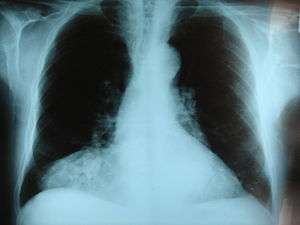

| Morgagni hernia seen on a chest radiograph. | |